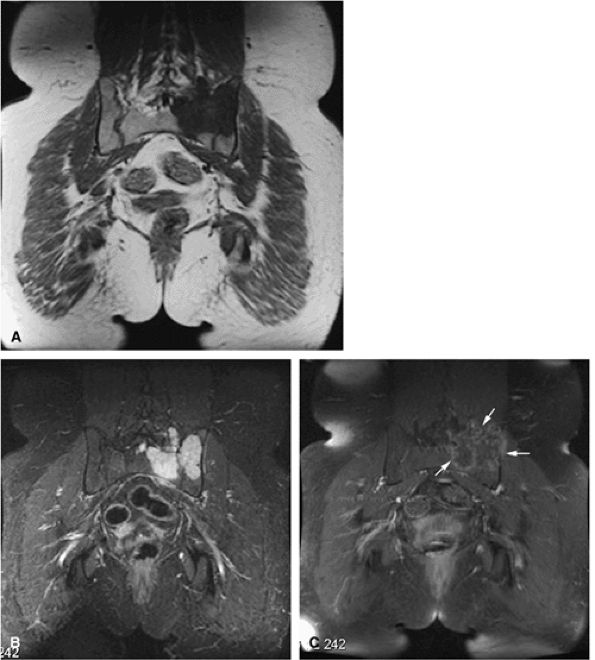

FIGURE 14-5 ● FDG-PET in the evaluation of patients with sarcomas. Whole-body FDG-PET scan (A) and corresponding axial image (B) in a patient with neurofibromatosis type 1 demonstrates a region of intense FDG uptake in the right buttock area (arrow), which was found to represent a malignant peripheral nerve sheath tumor arising in a neurofibroma. (C and D) Images from a whole-body FDG PET scan in a patient with osteosarcoma show intense FDG uptake in the proximal tibia (D) in the area of the tumor (arrow). Images of the chest and abdomen demonstrate no evidence of metastatic disease. A marker was placed over the left chest wall (C) (arrowhead). (E) Coronal, axial, and sagittal images of a whole-body FDG-PET scan in a patient with osteosarcoma of the right femur. The patient underwent resection of the right femur and total knee arthroplasty. MR images and CT scans were deemed inadequate for tumor evaluation because of metallic artifact. FDG-PET scan shows a cold defect in the region of the right knee arthroplasty (arrows) and no increased FDG uptake in the area of the right femur and knee.